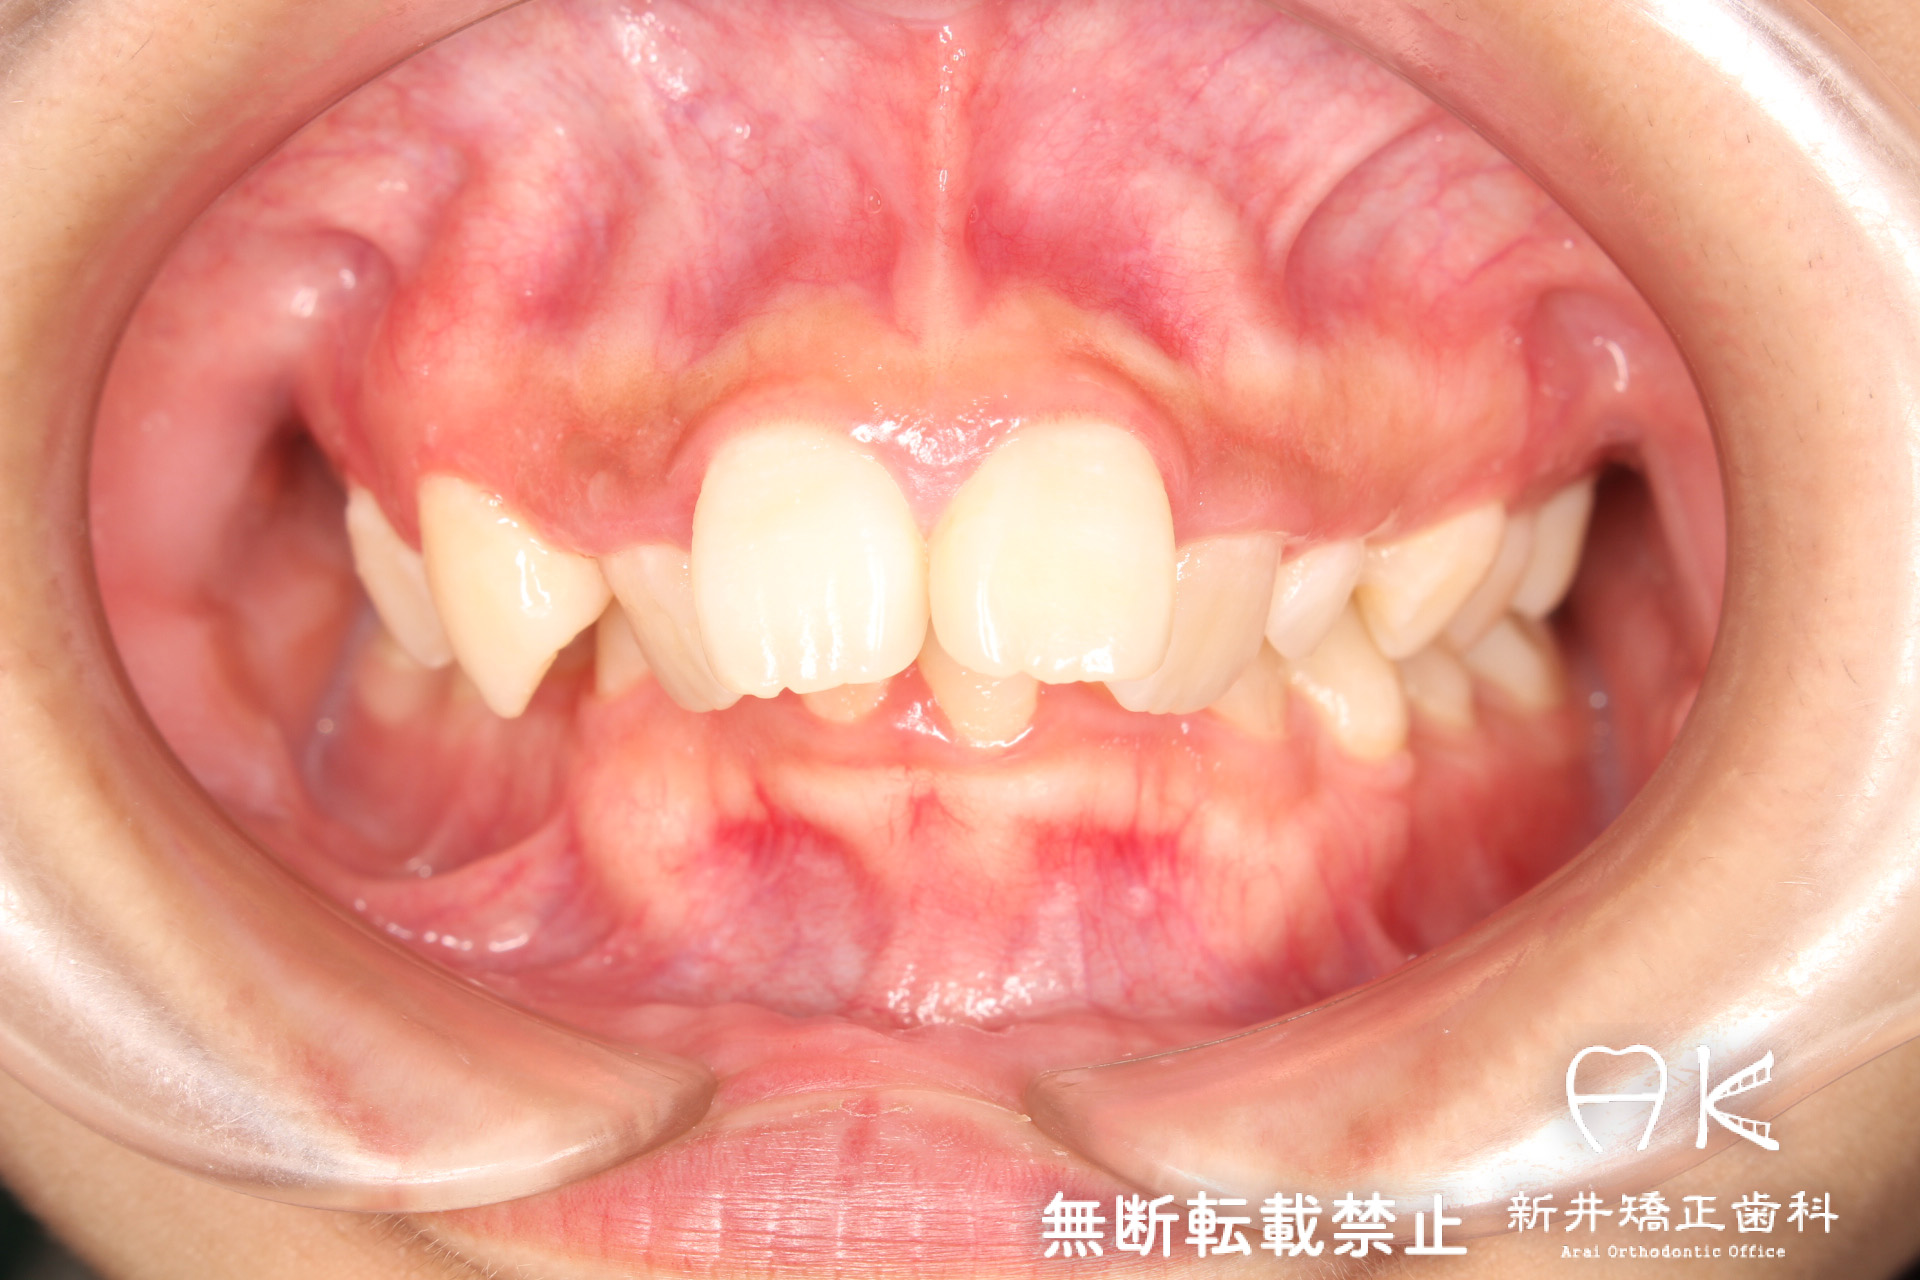

| 治療前 | 骨格的には受け口の患者さんですが、上顎前歯の唇側傾斜が大きく、患者さんとしては出っ歯だと思われていたパターンです。 元々口元の突出感はほとんどなかったため、歯を抜かずに上下顎ともに歯列を後方に移動させることにより主訴を改善させることとしました。 |

| 治療後 | 前歯から奥歯まで全体的に緊密な咬み合わせになっています。 治療前後のセファログラムのトレースの重ね合わせを比較すると、上下の歯列の後方移動ができ、それにより口元もよりすっきりしました。 また前歯の唇側傾斜も改善されています。 |